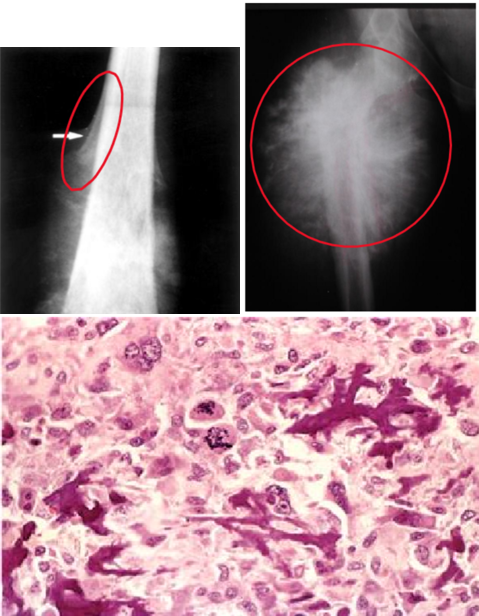

osteosarcoma

most common primary bone cancer arises in the metaphyseal cancellous bone & lifts the periosteum → Codman triangle on X-ray & sunburst also seen X-ray

mainly affects young males around knee area (distal femur or proximal tibia) presenting with pain & progressive swelling

seen in older males with predisposing factors: Paget disease, bone infarcts, & prior radiation (secondary type)

large bulky tumors that often contains areas of hemorrhage & cystic degeneration

tumor cells: very in size & shape (pleomorphic) & frequently have large hyperchromatic nuclei

osteoblastic type can produce bone

chemotherapy followed by surgery

with treatment: 5-year disease-free survival rate 60 - 70%

< 20% 5-year survival rate with overt metastasis or recurrent disease